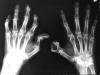

Artritis psoriásica y falange bífida.

Artritis psoriásica.